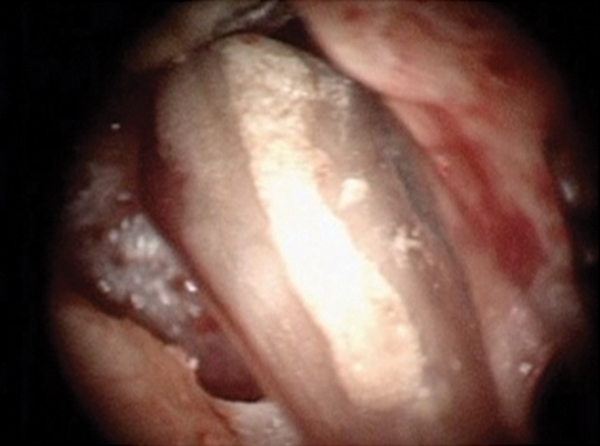

Figure 16. Post apicoectomy. Courtesy of Dr. Sam Kratchman.

Figure 16

Case 3: Apicoectomy and Retrofill

A patient presented with clinical symptoms and radiographic signs of post-endodontic disease (Figure 15). It was determined that the ledge on the mesial canals precluded retreatment and that an apicoectomy was to be performed. After locating the apicoectomy, it was possible to visualize both canals and an obvious isthmus between the two main canals (Figure 16). Retro-preparations were performed in the main canals, and the isthmus between them was grooved and the cavities filled with BC RRM-Putty (Figure 17). At the 20-month follow-up, the patient was asymptomatic and the radiograph showed complete healing (Figure 18).